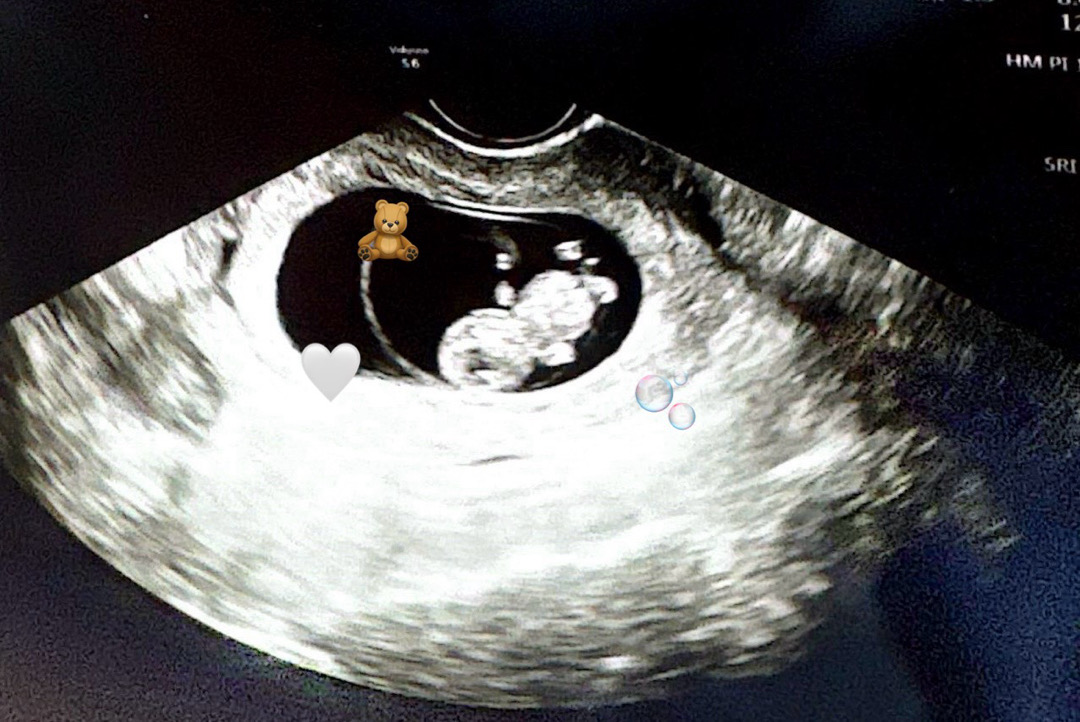

귀여운 젤리곰 모습 9주 2일차에 봤네요! 손발 꼬물거리는게 너무너무너무 귀여웠답니다 ㅜㅜ